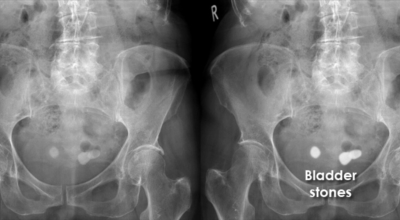

요로결석의 특징적인 증상으로 대개 진통제로도 멈추지 않는 심한 통증이 한쪽 및 양쪽 허리에 나타나며, 질 하복부나 고환 쪽으로 통증이 뻗칠 수 있답니다. 옆구리 통증은 신장 결석이나 방광 결석의 경우에는 잘 나타나지 않을 수 있으나 요관 결석의 경우 요의 흐름이 막히면서 통증이 나타날 수 있습니다. 요로결석의 통증은 맹장염과 비슷한 증상이라서 맹장염으로도 의심받을 수 있습니다.

방광 결석, 요도 결석은 소변 볼 때 심한 통증과 소변을 빈번히 보거나 잔뇨감 과 같은 증상이 나타날 수 있답니다. 요도 결석인 경우 심한 통증과 소변을 보지 못해 응급실을 가는 경우도 있습니다.